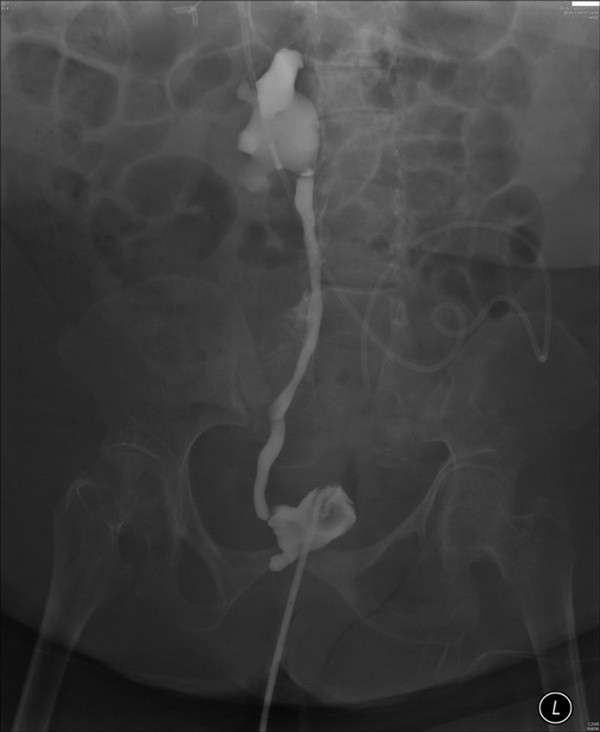

From screeningctisus.com

Leak from Suprapubic Catheter Genitourinary Case Studies CTisus CT Suprapubic Catheter Leaking From Site a suprapubic catheter (spc) is a device that drains urine from your bladder through your belly button. learn how to solve common catheter issues such as leakage, blockage, infection, and pain. Learn how it’s inserted, changed, and removed, and what to do and not do while you have. This may indicate either tube blockage or bladder spasms. Find. Suprapubic Catheter Leaking From Site.

Leak from Suprapubic Catheter Genitourinary Case Studies CTisus CT Suprapubic Catheter Leaking From Site a suprapubic catheter is a tube that drains urine from the bladder through a cut in the tummy. learn about the advantages, disadvantages and process of having a suprapubic catheter to drain the bladder, compared to a. a suprapubic catheter (spc) is a device that drains urine from your bladder through your belly button. learn how. Suprapubic Catheter Leaking From Site.